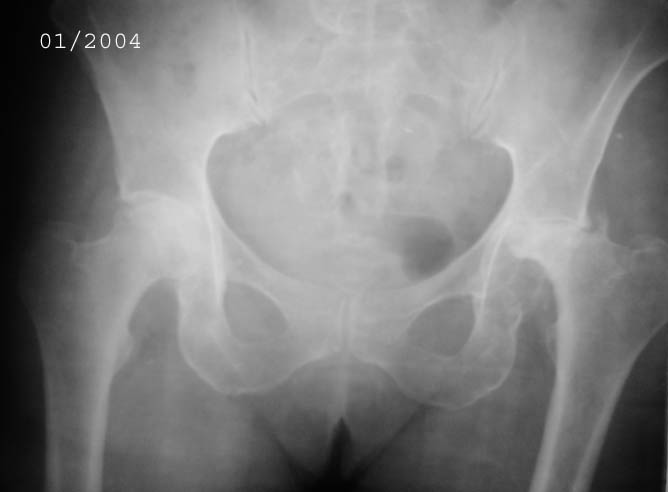

Уважаемые коллеги! Прошу Вас оказать консультативную помощь. Женщина, 44 года, инвалид 3 группы Диагноз: СКВ, асептический некроз головок обеих бедернных костей, двусторонний артроз 3-4 ст., болевой синдром, приводящая контрактура правого тазобедренного сустава,

хронический волчаночный гепатит, спленомегалия, анемия, СКВ с 2002 года (подтверждена наличием lupus-клеток), получала специфическую терапию, медрол 16 мг/сут. Боли в левом тазобедренном суставе появились в сентябре 2003 года. Динамика отражена на рентгенограммах. В марте 2004 года - синдром Мэллори-Вейса, кровотечение остановлено эндоскопически.

Ходит с тростью, хромота. Объем движений в суставах: справа - сгибание 90, разгибание 170, отведение 0, приведение 20, внутренняя ротация 15; слева - сгибание 90, разгибание 180, отведение 0, приведение 20, внутренняя ротация 0, наружная ротация 20.